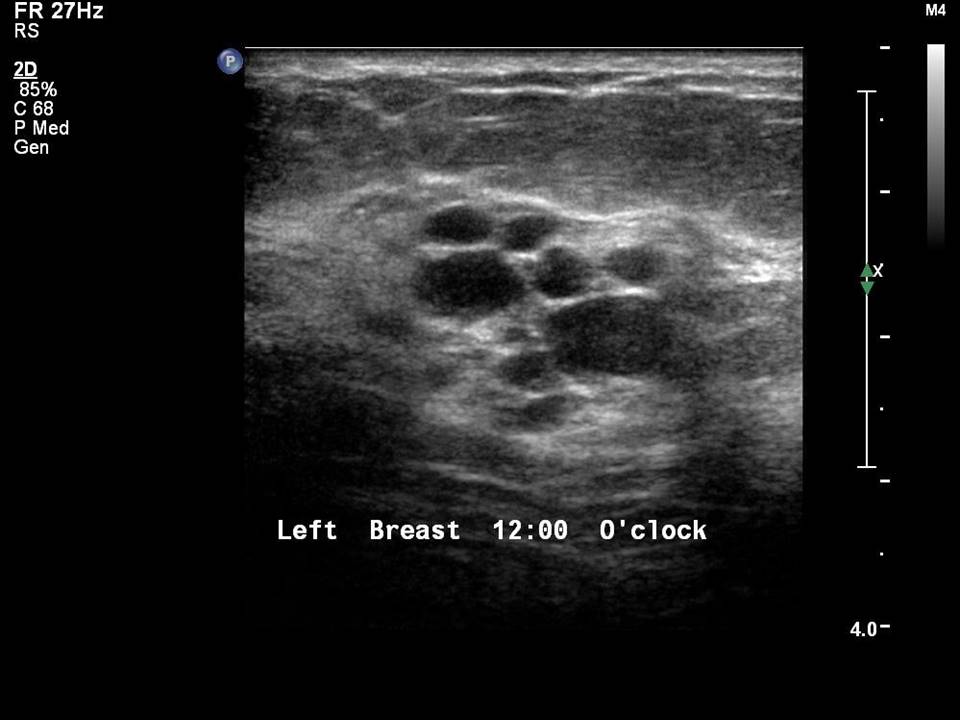

From www.cureus.com

Cureus Benign Breast Cyst in a Young Male Male Cyst In Breast Men have less breast tissue than women, so it may be easier to discover a lump. Here we describe the normal male breast anatomy and present an evaluation algorithm for the male patient with breast signs or symptoms. Healthy men typically have predominantly fatty tissue with few ducts and stroma [2], which is distinctly different from women's breasts where ducts,. Male Cyst In Breast.

Cureus Benign Breast Cyst in a Young Male Male Cyst In Breast The most common sign of breast cancer in men is a lump or swelling just under the nipple and areola. Less often, the lump is located in the upper outer quadrant of the breast. Male breast cancer is a rare cancer that begins as a growth of cells in the breast tissue of men. Benign simple breast cysts are commonly. Male Cyst In Breast.